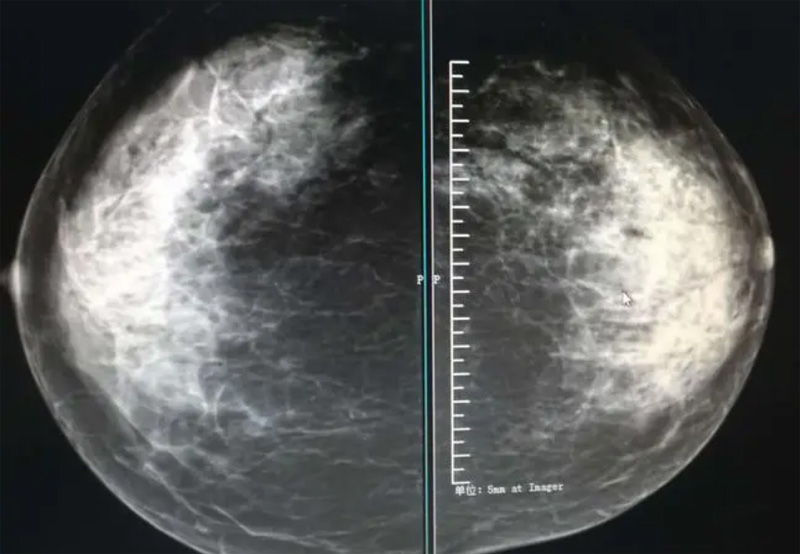

乳腺DR摄影体位有头尾位及内外侧斜位,乳房在片子的中央,乳头切线位,可见小部分胸大肌,内侧乳腺组织应全部包括在片中,外侧乳腺组织尽可能包括在片中。一张好的MLO位图像显示如下:乳房被推向前上,乳腺实质充分展开,胸大肌可见,较松弛,下缘达到乳头水平,乳头在切线位,部分腹壁包括在片中,但与下部乳腺分开,绝大部分乳腺实质显示在片中。乳腺组织外缘可见乳头的轮廓;乳腺后方的脂肪组织被很好地显示出来,乳房无皱褶。对于CC位及MLO位显示不良或未包全的乳腺实质,可以根据病灶位置的不同选择以下体位:外内侧位(LM)、内外侧位(ML)、内侧头尾轴位(MCC)、外侧头尾轴位(LCC),尾叶位(CLEO)及乳沟位。在临床实践中,对于常规体位上发现的异常改变,可以进一步采取一些特殊的摄影技术,包括局部加压摄影、放大摄影或局部加压放大摄影技术。

2、规范观图程序:屏幕软阅读或在专用日光观片灯下胶片阅读,后者应同时准备白炽强光灯及观片放大镜。注意双侧乳腺配对观察,推荐双眼横向扫描,进行双乳相同部位图像比较分析。

3、乳腺实质背景的确定:观察乳腺实质与脂肪的构成比例,了解乳腺实质类型,以判断对某些乳腺摄影征象敏感性的影响,有利于确定乳腺摄影对疾病的诊断价值。